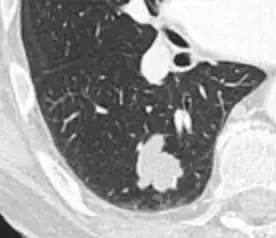

- Margin morphology: a spiculated margin is a risk factor for cancer.[8] Benign causes tend to have a well defined border, whereas lobulated lesions or those with an irregular margin extending into the neighbouring tissue tend to be malignant.[10] In particular, spiculations are highly predictive of malignancy with a positive predictive value up to 90%.[9] Also, a "notch sign", which is an abrupt indentation of the nodule, increases the risk of cancer, but may also be found in granulomatous diseases.[9]

-

subpleural nodule.[9] -

Round well-delineated solid lung nodule with smooth border.[9] -

Lobulated nodule.[9] -

Spiculated lung nodule.[9] -

A "notch sign".[9] -

A triangular perifissural node can be diagnosed as a benign lymph node.[9]